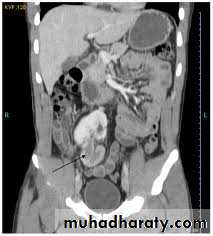

Abnormalities of renal ascent and fusion occur in weeks 6–9 of gestation, when the embryonic kidney is ascending to its definitive lumbar position (ascending as a result of rapid caudal growth of the embryo).Horseshoe kidney

This is the most common example of renal fusion. Prevalence is 1 in 400, with a male-to-female ratio 2:1. The kidneys lie vertically (instead of obliquely) and are joined at their lower poles (in 95%) by midline parenchymal tissue (the isthmus). The inferior mesenteric artery obstructs ascent of the isthmus. Consequently, the horseshoe kidney lies lower in the abdomen (at L3 or L4 vertebral level).

Normal rotation of the kidney is also prevented, thus the renal pelvis lies anteriorly, with the ureters also passing anteriorly over the kidneys and isthmus (but entering the bladder normally). Blood supply is variable, usually from one or more renal arteries or their branches, or from branches off the aorta or inferior mesenteric artery.

Most patients with horseshoe kidneys remain asymptomatic; however, infection and calculi may develop and cause symptoms.